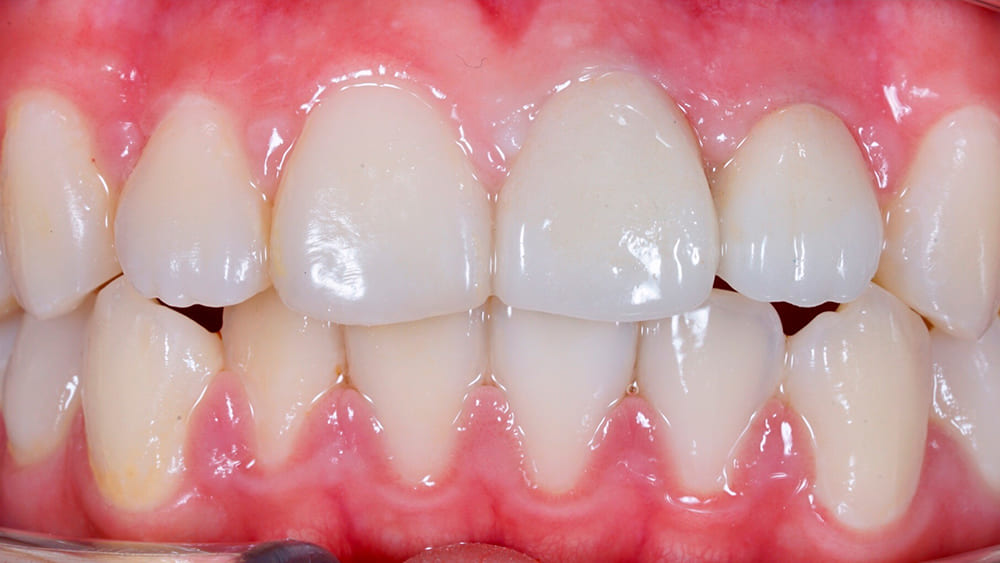

- Эстетика. Металлокерамические коронки выглядят так же естественно и натурально, как настоящие зубы.

Снаружи каркас покрыт слоем керамической массы. По цвету керамика полностью идентична натуральному тону эмали и подбирается индивидуально под каждого пациента.